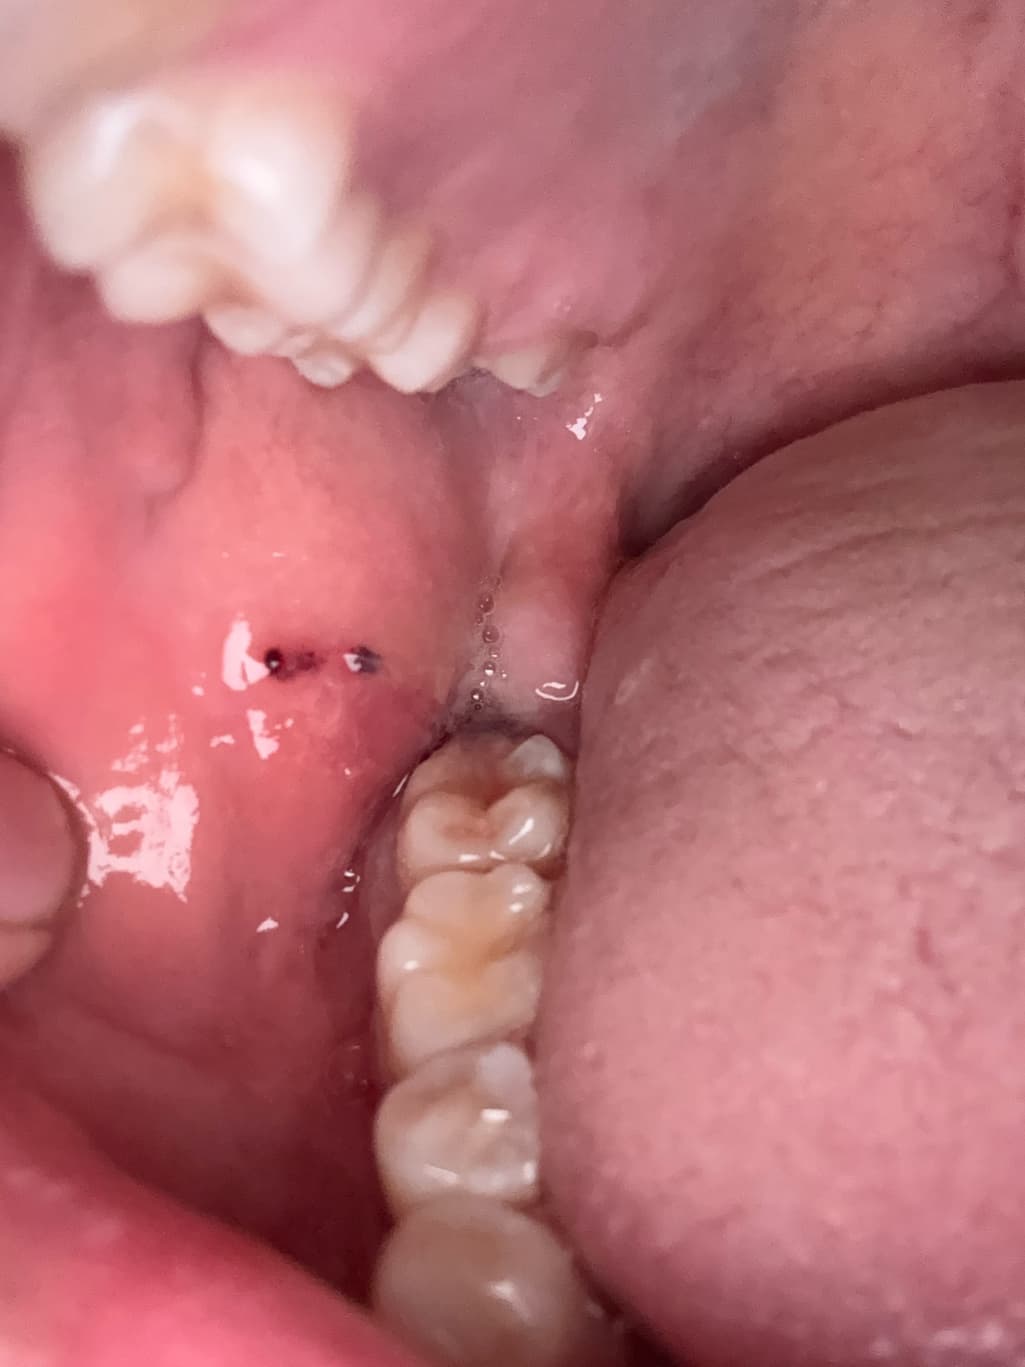

어제 사랑니뽑은 자리에 피떡이 생긴건 좋은데 오늘보니 그 위로 무언가 하얗게 덮어져있더라구요 이게뭔가요???

사랑니를 발치하고 나면 발치한 부위가 아물면서 가피등이 형성될수 있습니다. 이런 가피는 하얀색으로 보이는 경우도 있습니다.

문제가 되는것은 아니며 발치한 부위가 자극이 되지 않도록하는것이 좋습니다.

발치한 부위가 아무는데는 보통 2주정도의 시간이 걸리게 됩니다.

어제 사랑니뽑은 자리에 피떡이 생긴건 좋은데 오늘보니 그 위로 무언가 하얗게 덮어져있더라구요 이게뭔가요??? 치유 과정중에 생기는 부산물입니다